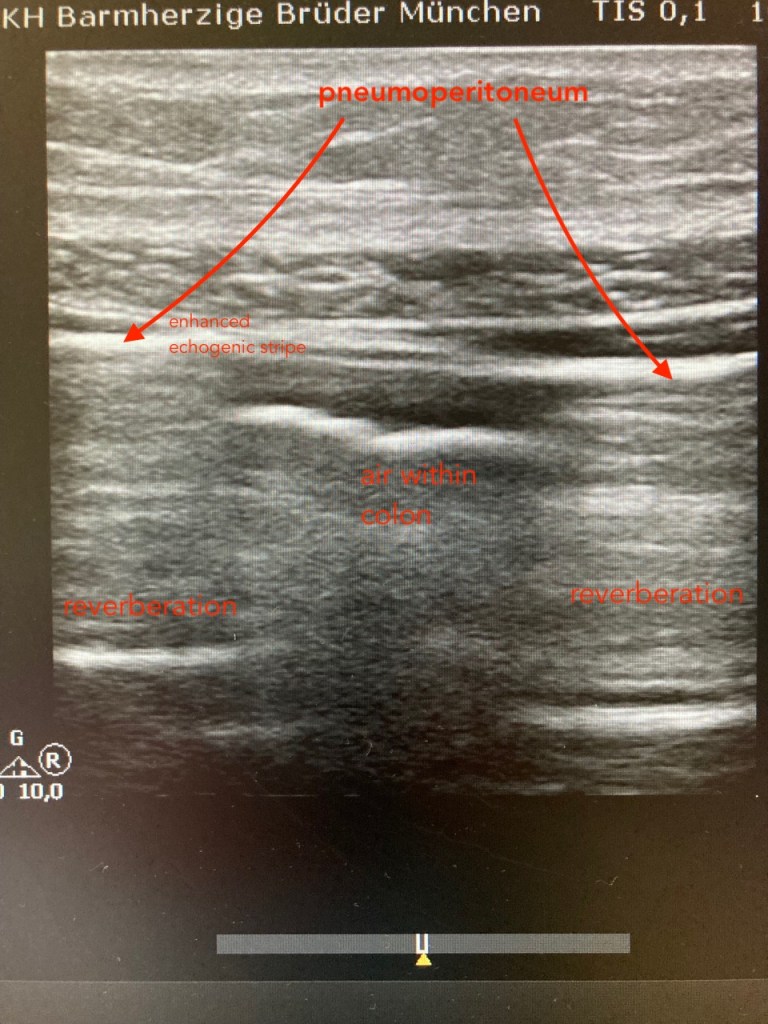

Sonographic detection of pneumoperitoneum:

The presence of air in abnormal locations scatters the ultrasound waves at the interface of soft tissue and air resulting in an enhanced peritoneal stripe sign, ring-down artefacts and acoustic shadows resembling “comet tails”.

The shifting phenomenon of movement of free intraabdominal air with patient position changes is strong sonographic evidence to support the presence of free air in the abdomen.

A linear array transducer (10–12 MHz) would be preferable over the standard curvilinear probe (2–5 MHz) owing to its superior near-field resolution.